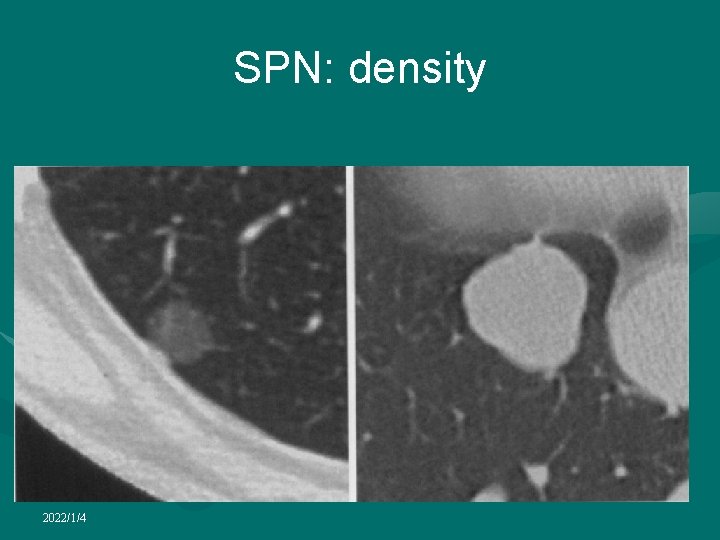

SPN: density 2022/1/4

Solitary pulmonary nodule • CT is almost always obtained in the diagnostic work-up of SPN • Radiological factors most often considered useful in determining nature of a SPN: • lesion size • Nodule margins and contours can be classified as smooth, lobulated, irregular, or spiculated • growth rate • presence of calcification 2022/1/4

Solitary pulmonary nodule • Presence of calcification within a SPN is generally a reliable sign of benignancy • Benign types of calcification include diffuse, those with a central nidus, laminated or popcorn • While stippled or eccentric calcification may be present in as many as 10% of malignant lung neoplasms • CT is more sensitive than radiography in the detection of calcification • Measuring CT number can allow the detection of calcifications invisible on CT scans in some patients with benign nodules (CT nodule densitometry) • Pixels denser than 200 HU usually indicate the presence of calcifications 2022/1/4

Solitary pulmonary nodule • By detecting the presence of fat, CT may be helpful in diagnosing pulmonary hamartoma, or other benign lesions such as lipoid pneumonia • Certain lesions in the lung may display the nonspecific features of an SPN on chest radiography, while CT may identify specific diagnostic features 2022/1/4